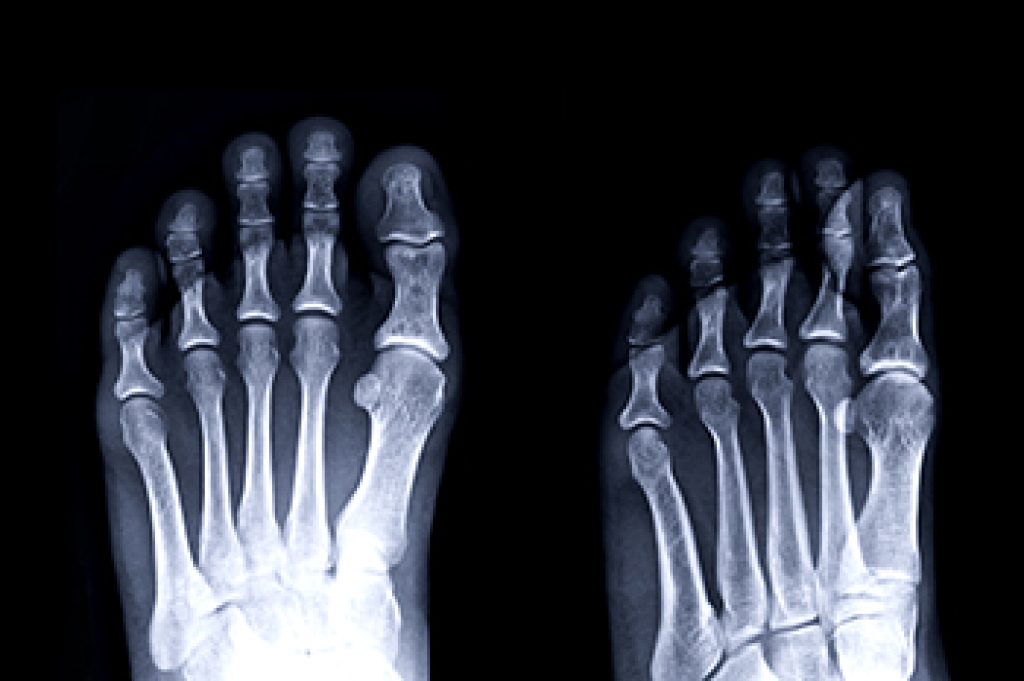

Understanding the biomechanics of the human foot can be exceedingly helpful to individuals seeking to improve their ability to care for their feet. One important biomechanical concept to understand about the feet is how the forefoot functions. The forefoot is described as encompassing the ligaments, muscles, and metatarsal bones located at the front part of the foot. Also within the forefoot are the phalanges, also known as toe bones. There are many other important bones and entities that make up the forefoot and serve important functions. For example, the sesamoid bones located underneath the base of the big toe joint are also found within the forefoot. Certain afflictions of the foot can have a particular impact on the forefoot. Namely, sesamoiditis, toe pain, hammertoe, and claw toe all primarily affect the area. For more information about the forefoot, contact a podiatrist today.